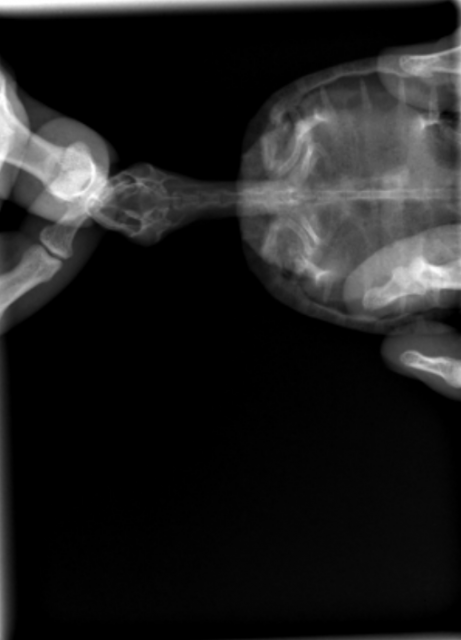

Пришли результаты рентгена по Малышу

Screenshot_20240330-161518.png